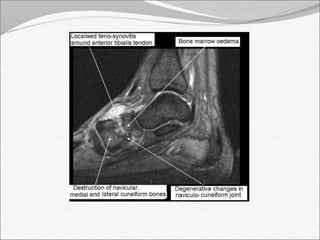

MRI findings:

• Synovial enhancement

• Perisynovial edema and joint effusion.

• Single or multiple radiolucent abscesses

• Assessment of the extent of tissue affected

MRI findings: •Synovial enhancement • Perisynovial edema and joint effusion. • Single or multiple radiolucent abscesses • Assessment of the extent of tissue affected